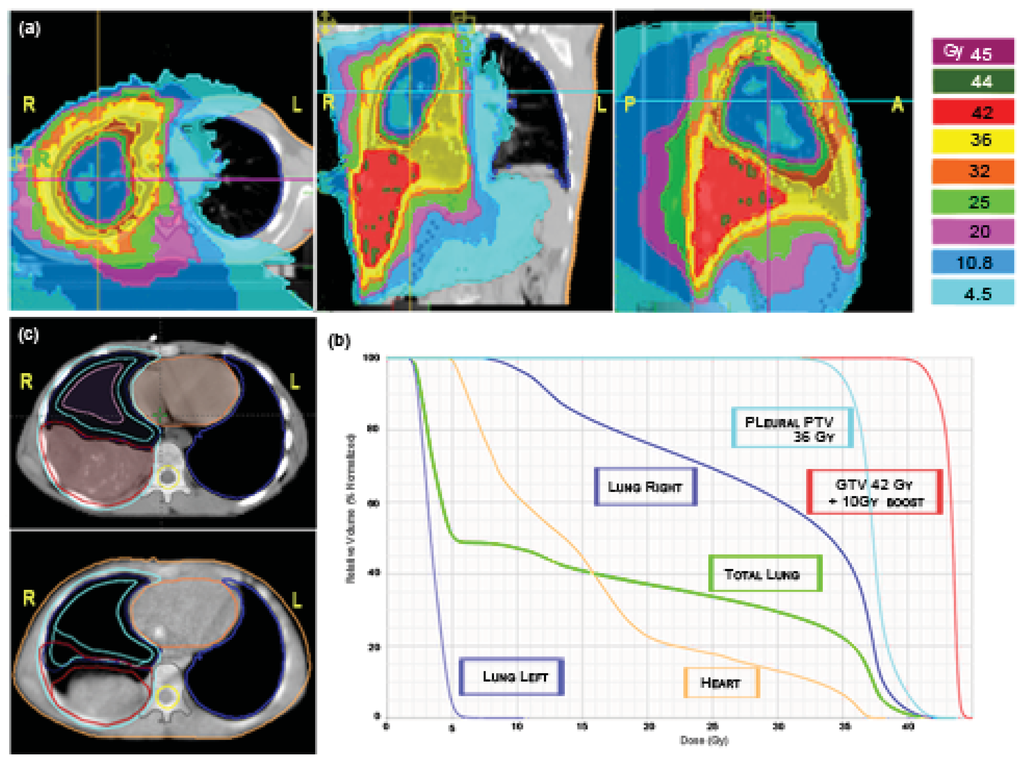

Irradiation of the pleural cavity represents a special challenge for radiotherapists because every conventional technique determines the risk of delivering high doses to the involved lung. Even if this treatment is mostly applied in the adult population with mesothelioma, sometimes also pediatric age cases of soft tissue tumors can involve the entire pleura. We applied HT to an adolescent patient affected by PNET (primitive neuroectodermal tumor) of the right pleural cavity with multiple nodular localizations and, after chemotherapy, a residual bulky disease along the base of the diaphragm. The patient was simulated in a supine position with arms overhead and fixed with a vacuum bag. The prescription to the right pleural PTV was: first phase, 36Gy in 20 fractions with a simultaneous integrated boost of 42 Gy in 20 fractions to the post-chemotherapy residual disease [Figure 8(a)]; second phase, 10 Gy in five fractions (total dose 52 Gy) delivered only to the shrinking residual costal-diaphragmatic tumor [Figure 8(c)]. The planning was built with the following constraints: mean total lung dose <20 Gy; V20 Gy total lung <30–35%; left healthy lung, all volume <15 Gy, V5 Gy <50%; heart V 20Gy <50%. A tune structure was built in the central part of the affected lung with a dose constraint of 20 Gy [24]. The result was quite good both in terms of PTV coverage and the sparing of the contra-lateral lung and other OARs [Figure 8(a)]. The mean total lung dose and the V5 Gy were 15.9 Gy and 50%, respectively. The mean dose for the affected lung was 29.1 Gy. The maximum dose, the mean dose and the V5 Gy for the healthy lung were 10.5 Gy, 3.4 Gy and 3.8%, respectively. The maximum dose, the mean dose and the V20 Gy for the heart were 38.2 Gy, 15.5 Gy and 22%, respectively [Figure 8(b)]. The plan was initially defined on the basis of pre-RT imaging, but this could not accurately reflect the degree of normal lung exposure during all treatment. For this reason, while monitoring tumor shrinkage with daily MV-CT, we planned the second treatment phase on the basis of MV-CT acquisition, applying an adaptive therapy to try to further reduce any exposure to the normal lung [Figure 8(c)]. The patient is in complete remission after 42 months from end of RT. He developed a transient radiation pneumonitis in the right lung during the first year, requiring steroid support.